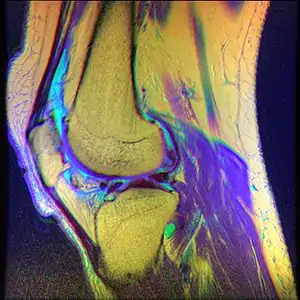

Chondromalacia patellae (also known as CMP) is an inflammation of the underside of the patella and softening of the cartilage.

The cartilage under the kneecap is a natural shock absorber, and overuse, injury, and many other factors can cause increased deterioration and breakdown of the cartilage. The cartilage is no longer smooth and therefore movement and use is very painful.[1] While it often affects young individuals engaged in active sports, it also afflicts older adults who overwork their knees.[2][3]

While the term chondromalacia sometimes refers to abnormal-appearing cartilage anywhere in the body,[9] it most commonly denotes irritation of the underside of the kneecap (or "patella"). The patella's posterior surface is covered with a layer of smooth cartilage, which the base of the femur normally glides smoothly against when the knee is bent. However, in some individuals the kneecap tends to rub against one side of the knee joint, irritating the cartilage and causing knee pain.[10]